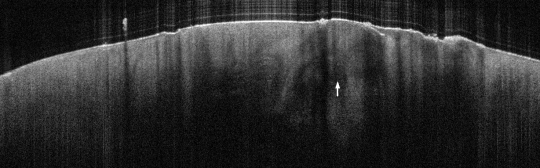

VA129: Left Forearm, Squamous Cell Carcinoma, Invasive, Keratoacanthoma Type

- Arrow indicates keratin mass